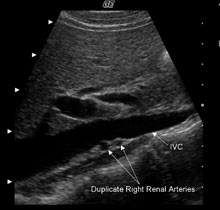

Variantele anatomice sunt relativ frecvente la nivelul vaselor renale. Aproximativ 30% din indivizi au mai mult de o artera renala. Arterele supranumerare pot aparea bilateral sau unilateral. Cele mai multe artere renale accesorii au origine in aorta abdominala, dar se pot desprinde si din arterele iliaca comuna, mezenterica superioara, mezenterica inferioara, suprarenala sau hepatica dreapta. Ramificarea precoce a arterei renale apare in aproximativ 15% din cazuri.

Figura 4 - Imagine sagitala in nuante de gri si imagine coronala color la doi pacienti cu artere supranumerare drepte. Pentru identificarea arterelor renale multiple, este utila obtinerea unei imagini a VCI in axul sau lung. O examinare atenta dedesubtul VCI evidentiaza doua artere renale drepte (A) si trei artere renale drepte (C). O alta imagine utila pentru a demonstra existenta arterelor renale supranumerare este o imagine coronara a aortei. Aceasta vedere asigura un unghi excelent pentru identificarea originii arterelor renale drepte si stangi folosind Doppler color. Figura B arata doua artere renale drepte si una stanga folosind power Doppler. Cum power Doppler nu arata directia fluxului, vena renala stanga are aceeasi culoare cu artera si poate fi usor luata drept o a doua artera renala stanga. O examinare atenta arata totusi ca vasul nu are origine in aorta, ci trece anterior de ea. Power Doppler a fost folosit si in cazul figurii D pentru a demonstra prezenta a 3 artere renale drepte si una stanga. |